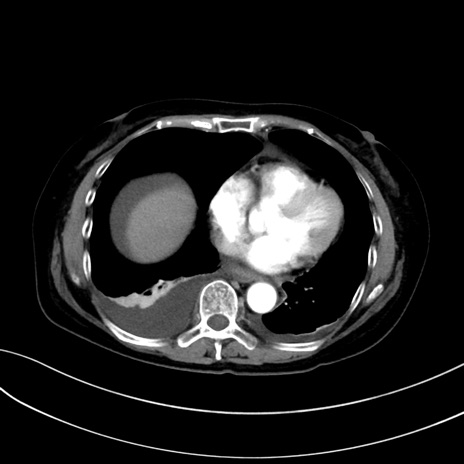

(冠状断像)1日半後